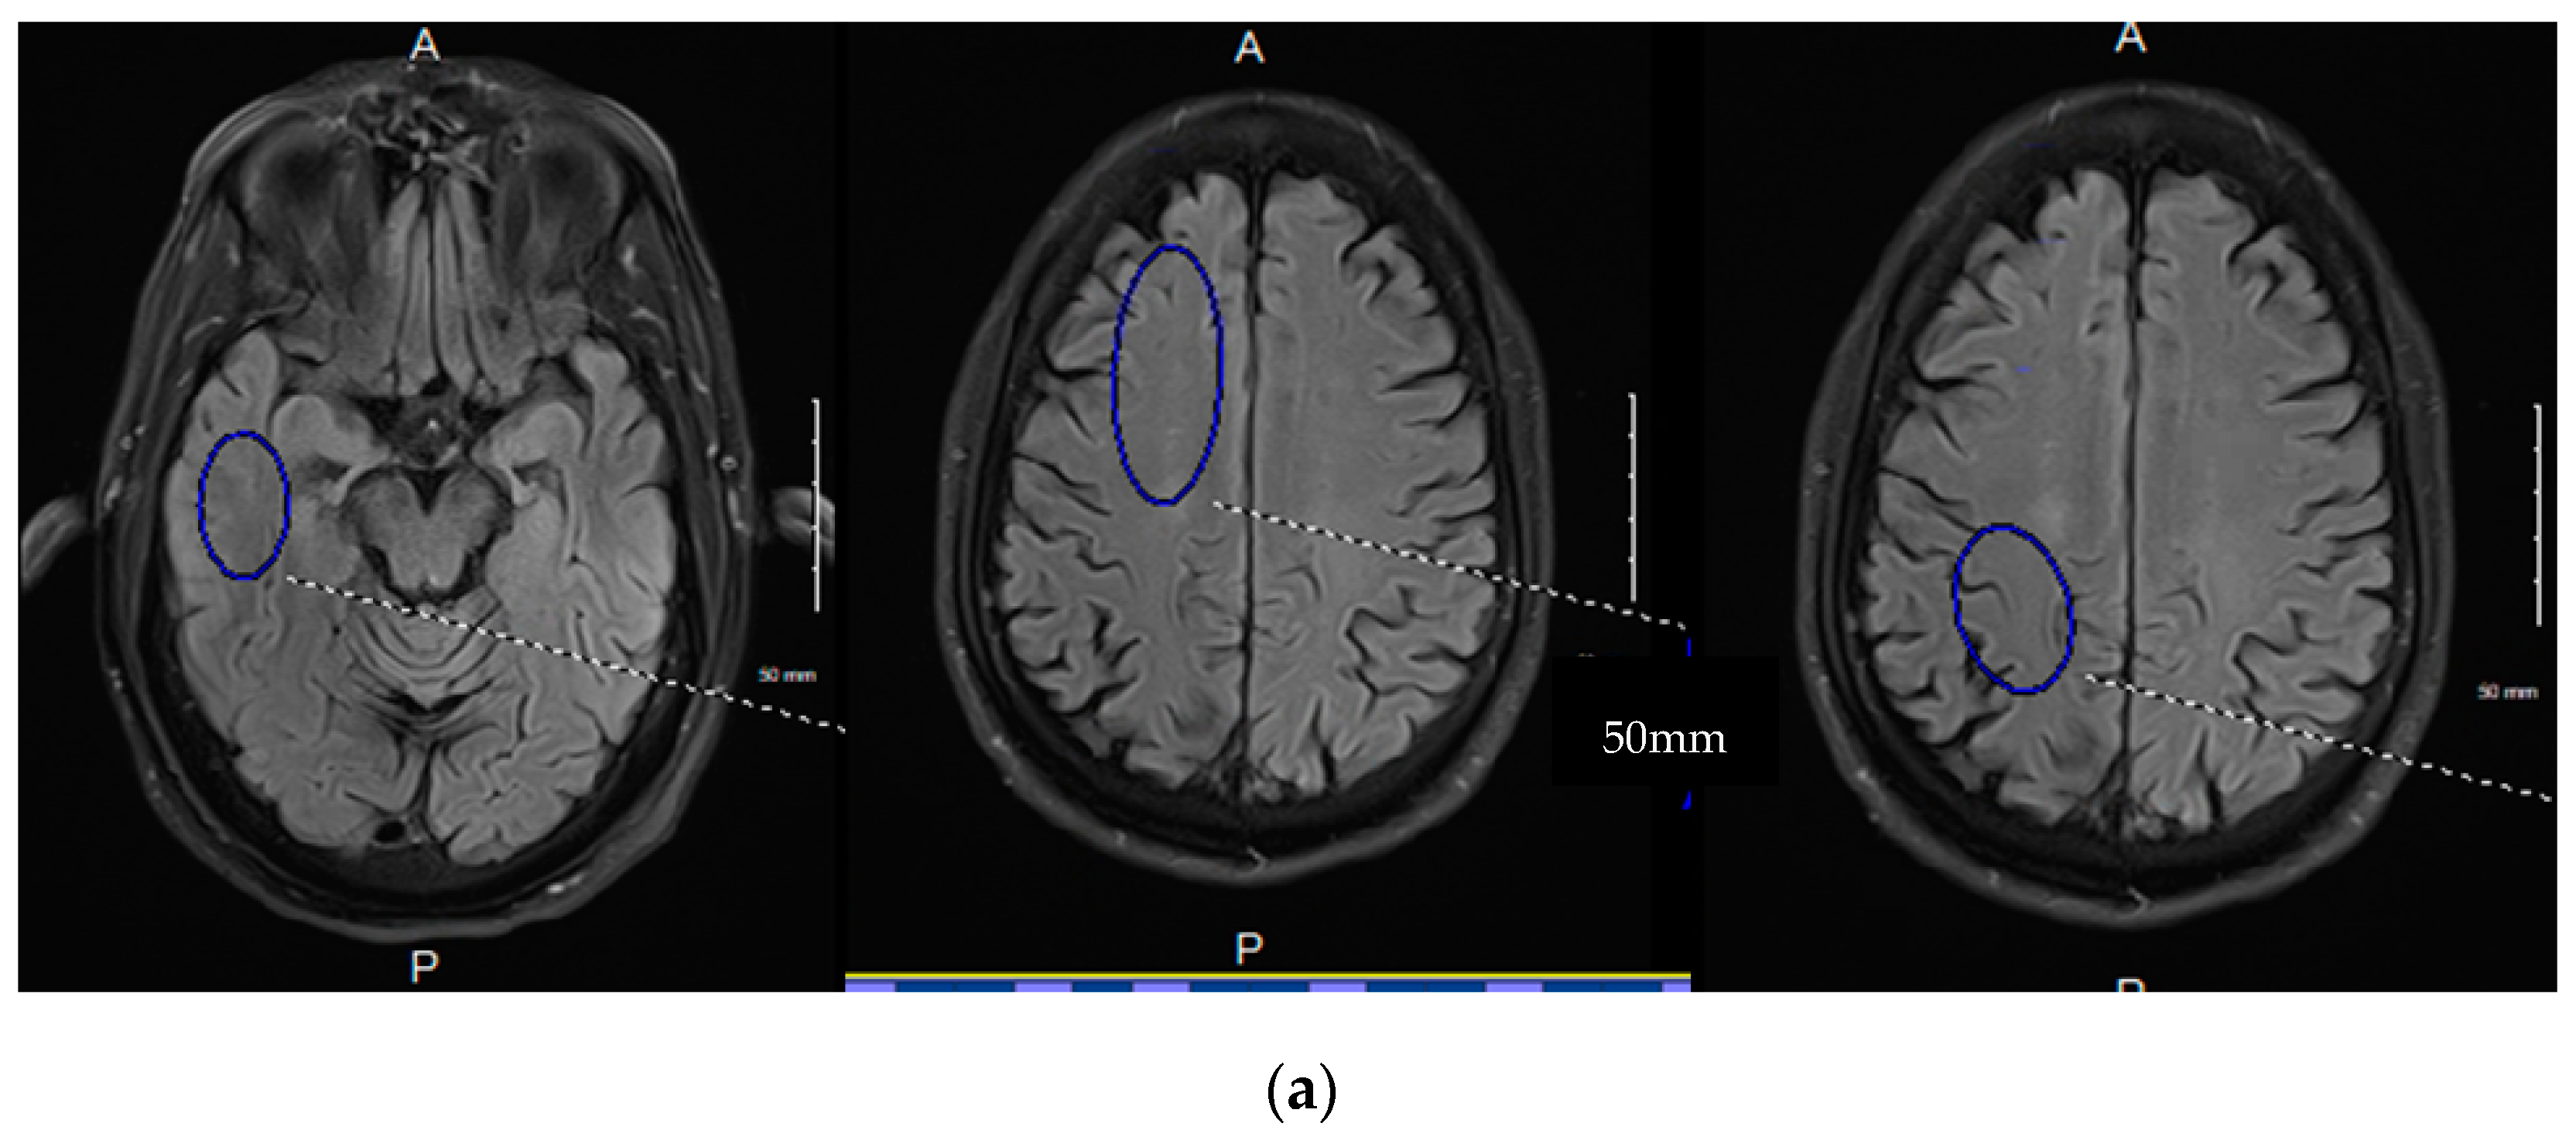

- Joseph, C.R.; Lim, J.K.; Grohol, B.N.; Zivcevska, M.; Lencke, J.; Rich, E.D.; Arrasmith, C.J. Identifying delay in glymphatic clearance of labeled protons post-acute head trauma utilizing 3D ASL MRI (arterial spin labeling): A pilot study. Sci. Rep. 2024, 14, 6188. [Google Scholar] [CrossRef]

- Joseph, C.R.; Benhatzel, C.M.; Stern, L.J.; Hopper, O.M.; Lockwood, M.D. Pilot study utilizing MRI 3D TGSE PASL (arterial spin labeling) differentiating clearance rates of labeled protons in the CNS of patients with early Alzheimer disease from normal subjects. Magn. Reson. Mater. Phys. Biol. Med. 2020, 33, 559–568. [Google Scholar] [CrossRef]

- Joseph, C.R.; Kreilach, A.; Reyna, V.A.; Kepler, T.A.; Taylor, B.V.; Kang, J.; McCorkle, D.; Rider, N.L. Utilizing Reduced Labeled Proton Clearance to Identify Preclinical Alzheimer Disease with 3D ASL MRI. Case Rep. Neurol. 2023, 15, 177. [Google Scholar] [CrossRef]